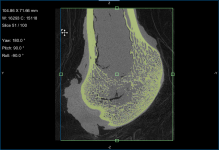

Comparison of volume fraction scalar map (on left) with vector-based field of anisotropy (on right)